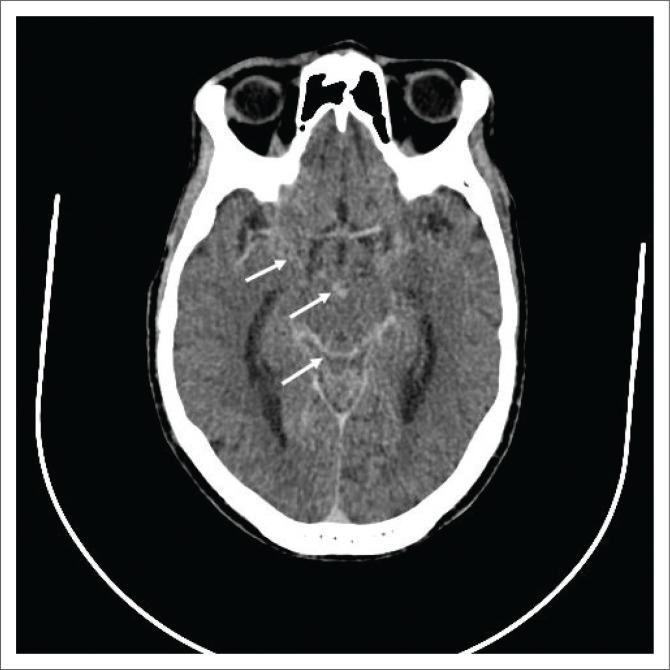

Extra-pulmonary tuberculosis (EPTB), caused by , is the leading cause of communicable disease-related deaths in people with human immunodeficiency virus (HIV) worldwide and in South Africa. disseminates haematogenously from an active primary lung focus and may affect extra-pulmonary sites in up to 15% of patients. Extra-pulmonary TB may present with a normal chest radiograph, which often causes a significant diagnostic dilemma. This review describes the main sites of involvement in EPTB, which is illustrated by local imaging examples.

由……引起的肺外结核病(EPTB)是全球和南非人类免疫缺陷病毒(HIV)感染者中与传染病相关死亡的主要原因。……从活跃的原发性肺部病灶经血行播散,高达15%的患者可能累及肺外部位。肺外结核病可能胸部X线片表现正常,这常常造成重大的诊断困境。本综述描述了肺外结核病的主要受累部位,并通过局部影像学实例进行说明。 (注:原文中“caused by ”和“disseminates haematogenously from an active primary lung focus and may affect extra-pulmonary sites in up to 15% of patients.”前缺失关键信息)